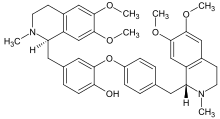

Dimer alkaloids

In addition to the described above monomeric alkaloids, there are also dimeric, and even trimeric and tetrameric alkaloids formed upon condensation of two, three, and four monomeric alkaloids. Dimeric alkaloids are usually formed from monomers of the same type through the following mechanisms:[193]

- Oxidative addition of phenols (dauricine, tubocurarine)